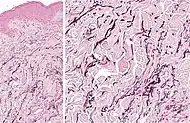

Thick elastic fibers consisting of bundles of elastin in the human lung

Elastin is a protein that in humans is encoded by the ELN gene. Elastin is a key component of the extracellular matrix in gnathostomes (jawed vertebrates).[3] It is highly elastic and present in connective tissue allowing many tissues in the body to resume their shape after stretching or contracting.[4] Elastin helps skin to return to its original position when it is poked or pinched. Elastin is also an important load-bearing tissue in the bodies of vertebrates and used in places where mechanical energy is required to be stored.[5]